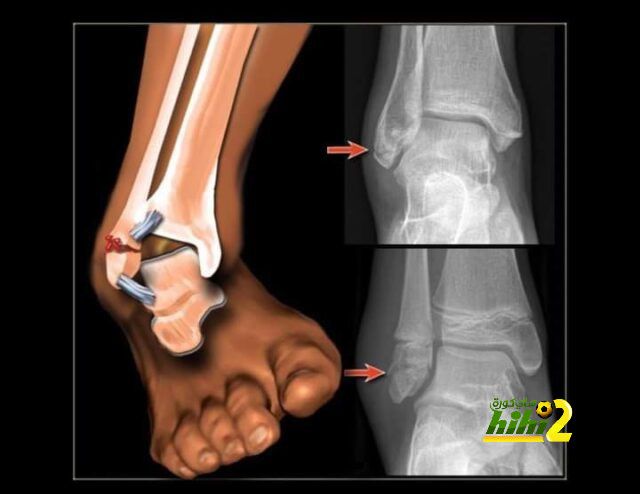

شرح إصابة إليوت طبيا